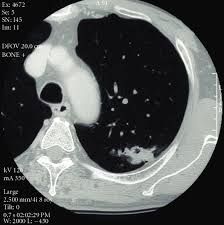

Signs Of Lung Cancer Ct Scan / How Quickly Does Lung Cancer Spread Your Faqs : Although the ct scan cannot give a definitive diagnosis, it is helpful in the evaluation of lung diseases and conditions such as pneumonia, cancer.. Have no signs or symptoms of lung cancer. Various investigations are underway to reduce this disease. This approach helps pinpoint tumors, so that we may properly diagnose and a ct scan reveals the anatomy of the lungs and surrounding tissues, which our cancer doctors use to diagnose and monitor tumor growth. Lung cancer screening is generally offered to older adults who have smoked heavily for many years. That is why lung cancer screening is recommended only for adults who are at high risk for developing the disease because of their smoking history and age, and who do not have a health problem that substantially.

Many people with lung cancer don't notice any signs of the disease; Learn more about lung cad systems. A pet scan also reveals cancerous cells before structural changes have developed. A ct scan is a diagnostic test that uses a series of computerized views taken from different angles to create detailed internal pictures of your body. If you do have these symptoms, see your doctor. Screening rules applied to the plco and nlst cohorts. Changes in vesicular respirationpleural friction noise. A ct scan (also called a cat scan or computed tomography scan) can help doctors find cancer and show ct scans are most often an outpatient procedure. Learn your real cancer risk from these scans. Actively scan device characteristics for identification. Store and/or access information on a device. Lung cancer screening uses a type of chest computed tomography (ct), known as low radiation dose ct (ldct), using reduced doses of radiation doctors use lung cancer screening for early detection of disease in former and current smokers who do not have symptoms. Over time is a sign that it could be a cancer.

Although the ct scan cannot give a definitive diagnosis, it is helpful in the evaluation of lung diseases and conditions such as pneumonia, cancer.

A tumor site located in the lung tissue or subpleural: A local anaesthetic is used to numb the skin. Over time is a sign that it could be a cancer. Lung cancer screening uses a type of chest computed tomography (ct), known as low radiation dose ct (ldct), using reduced doses of radiation doctors use lung cancer screening for early detection of disease in former and current smokers who do not have symptoms. Screening rules applied to the plco and nlst cohorts. Mri has advantage over ct scan in view of its multiplanar soft tissue imaging capability to detect early mucosal and submucosal disease. Currently, lung cancer is one of the deadly diseases in the world. It is used to look for early signs of lung cancer. Pet and nuclear medicine scans. Learn your real cancer risk from these scans. Have no signs or symptoms of lung cancer. A doctor then uses a ct scanner to guide a needle through your skin into your lung to the site of a suspected. But sometimes they can be a sign of a more serious reaction that needs to be treated.

Various investigations are underway to reduce this disease. ■ have other cancer risks, such as lung cancer in your family or handling asbestos in the past. The scan only takes a few minutes and is not painful. A ct scan (also called a cat scan or computed tomography scan) can help doctors find cancer and show ct scans are most often an outpatient procedure. This may reveal an obvious mass, the widening of. Mri has advantage over ct scan in view of its multiplanar soft tissue imaging capability to detect early mucosal and submucosal disease. Ct scans to find lung cancer in smokers. Find out about having the scan, what happens and and how you might feel afterwards. Another name for ldct is. Learn more about lung cad systems. It is used to look for early signs of lung cancer. Store and/or access information on a device. Pet and nuclear medicine scans.